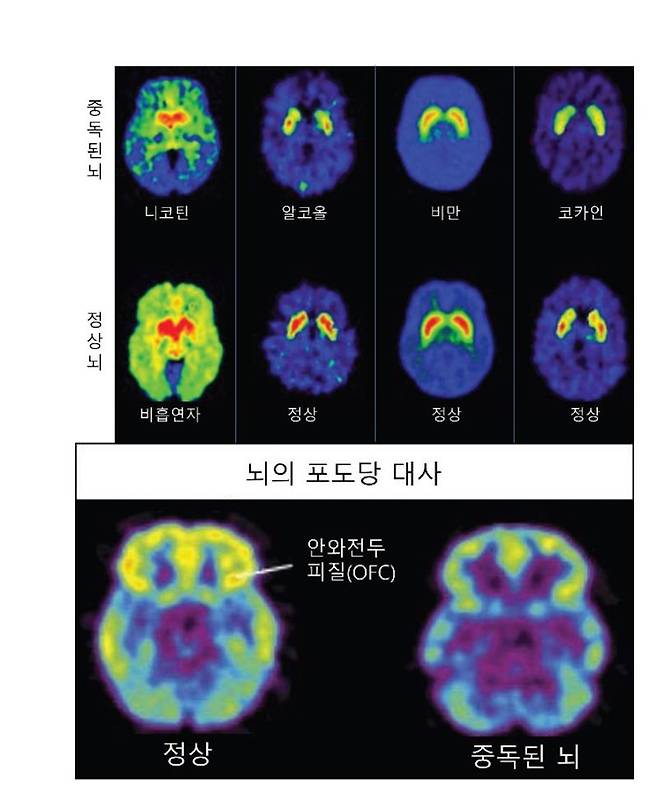

실제로 중독에 빠진 뇌는 정상 뇌와 상당한 차이가 있다. 양전자방출 단층촬영(PET) 뇌 사진을 보면 정상 뇌는 도파민 회로 중 하나인 선조체 부위에 도파민 수송체와 수용체가 상당량 존재한다. 그러나 무엇인가에 중독된 뇌는 이것들이 매우 적다. 중독 증상이 심할수록 도파민 수송체와 수용체는 거의 고갈되다시피 한다. 그만큼 많은 양의 도파민에 지속적으로 노출되어 도파민 회로가 고장 난 상태라고 말할 수 있다.

또한 중독된 뇌는 신진대사가 떨어진다. 포도당의 신진대사를 관찰하는 PET 사진에서 정상 뇌는 모든 부위가 활성화되어 있지만 중독된 뇌는 상당 부위에서 활동이 멈춘 것을 볼 수 있다.